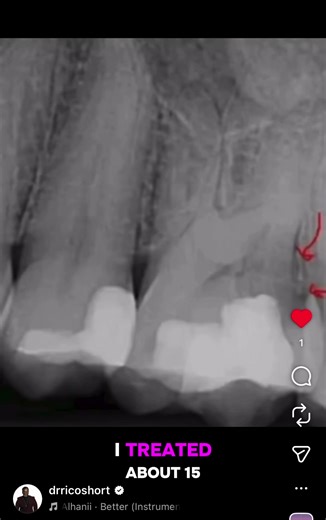

18 X-ray